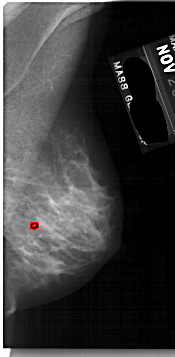

A_1736_1.RIGHT_CC

RIGHT_CC LINES 5146 PIXELS_PER_LINE 2071 BITS_PER_PIXEL 12 RESOLUTION 43.5 OVERLAY

FILE: A_1736_1.RIGHT_CC.OVERLAY

TOTAL_ABNORMALITIES 1

ABNORMALITY 1

LESION_TYPE CALCIFICATION TYPE PLEOMORPHIC DISTRIBUTION CLUSTERED

ASSESSMENT 3

SUBTLETY 1

PATHOLOGY BENIGN

TOTAL_OUTLINES 1

BOUNDARY